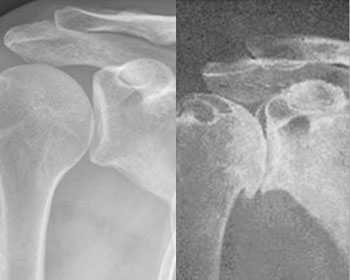

Периартроз плечевого сустава 2 стадия. Лечился у мануальщиков, пиявками, иглами - не помогло. Плазма вызвала регенерацию утраченных тканей. Вернулась полная подвижность, ушли хронические 15-летние боли. Срок лечения -10 дней.